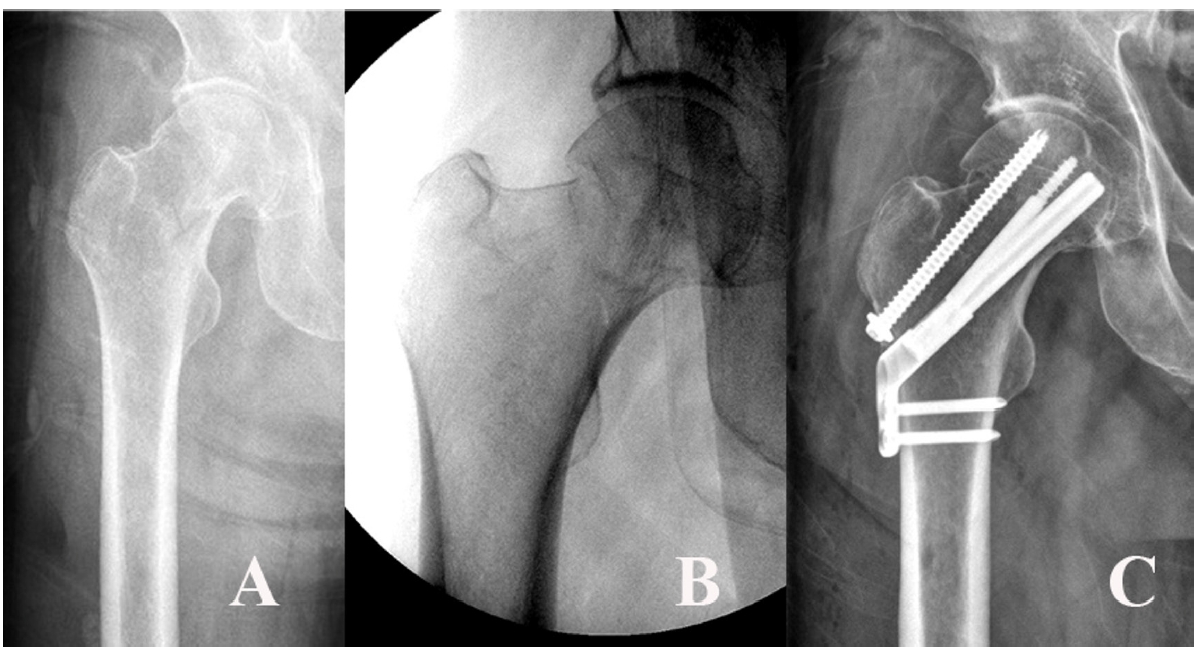

Fig. 10.

A 54-year-old male patient sustained a femoral neck fracture caused by a fall from a 2-m height. (A, B) Plain radiographs and an intraoperative fluoroscopic image show the subcapital fracture. (C) The femoral neck system anti-rotational screw was applied to increase the anchoring and stability of the femoral head fragment.

When compared between vertical fracture and basicervical fracture, the max VMS value of the implant was not significantly different, but it was much different at the fracture site. Thus, despite these prejudices, we think the vertical fracture might be more suitable for FNS fixation than the basicervical fracture. Furthermore, considering that 96% of vertical neck fractures had major comminution, which was mainly located inferiorly and posteriorly [30], the FNS for vertical fractures might be an appropriate implant for vertical fracture based on our results, which showed the lower stress distribution on the fracture site. Additionally, compared with the no-fracture model, the VMS distribution of the vertical fracture was most similar in the fracture site and implant. For the subcapital fracture, the stress distribution mainly concentrated on the implant, and the max points of VMS were the bolt around the fracture site. Based on this result, authors should assume that the anchoring between the proximal bolt and the cancellous bone of the femoral head is maximized. In the personal communication between orthopedic trauma surgeons, we found that fixation failure of FNS was not uncommon, although the critical factors could not be analyzed. However, this FE analysis seems to show that the proximal osseous anchoring of the bolt might be essential for maintaining rotational and angular stability. The subcapital fracture might be cautiously applied because the femoral head fragment had a short working length. Adding an anti-rotational screw to the FNS might increase the proximal anchoring and angular stability, so further research on this topic will be performed in the future (Fig. 10).